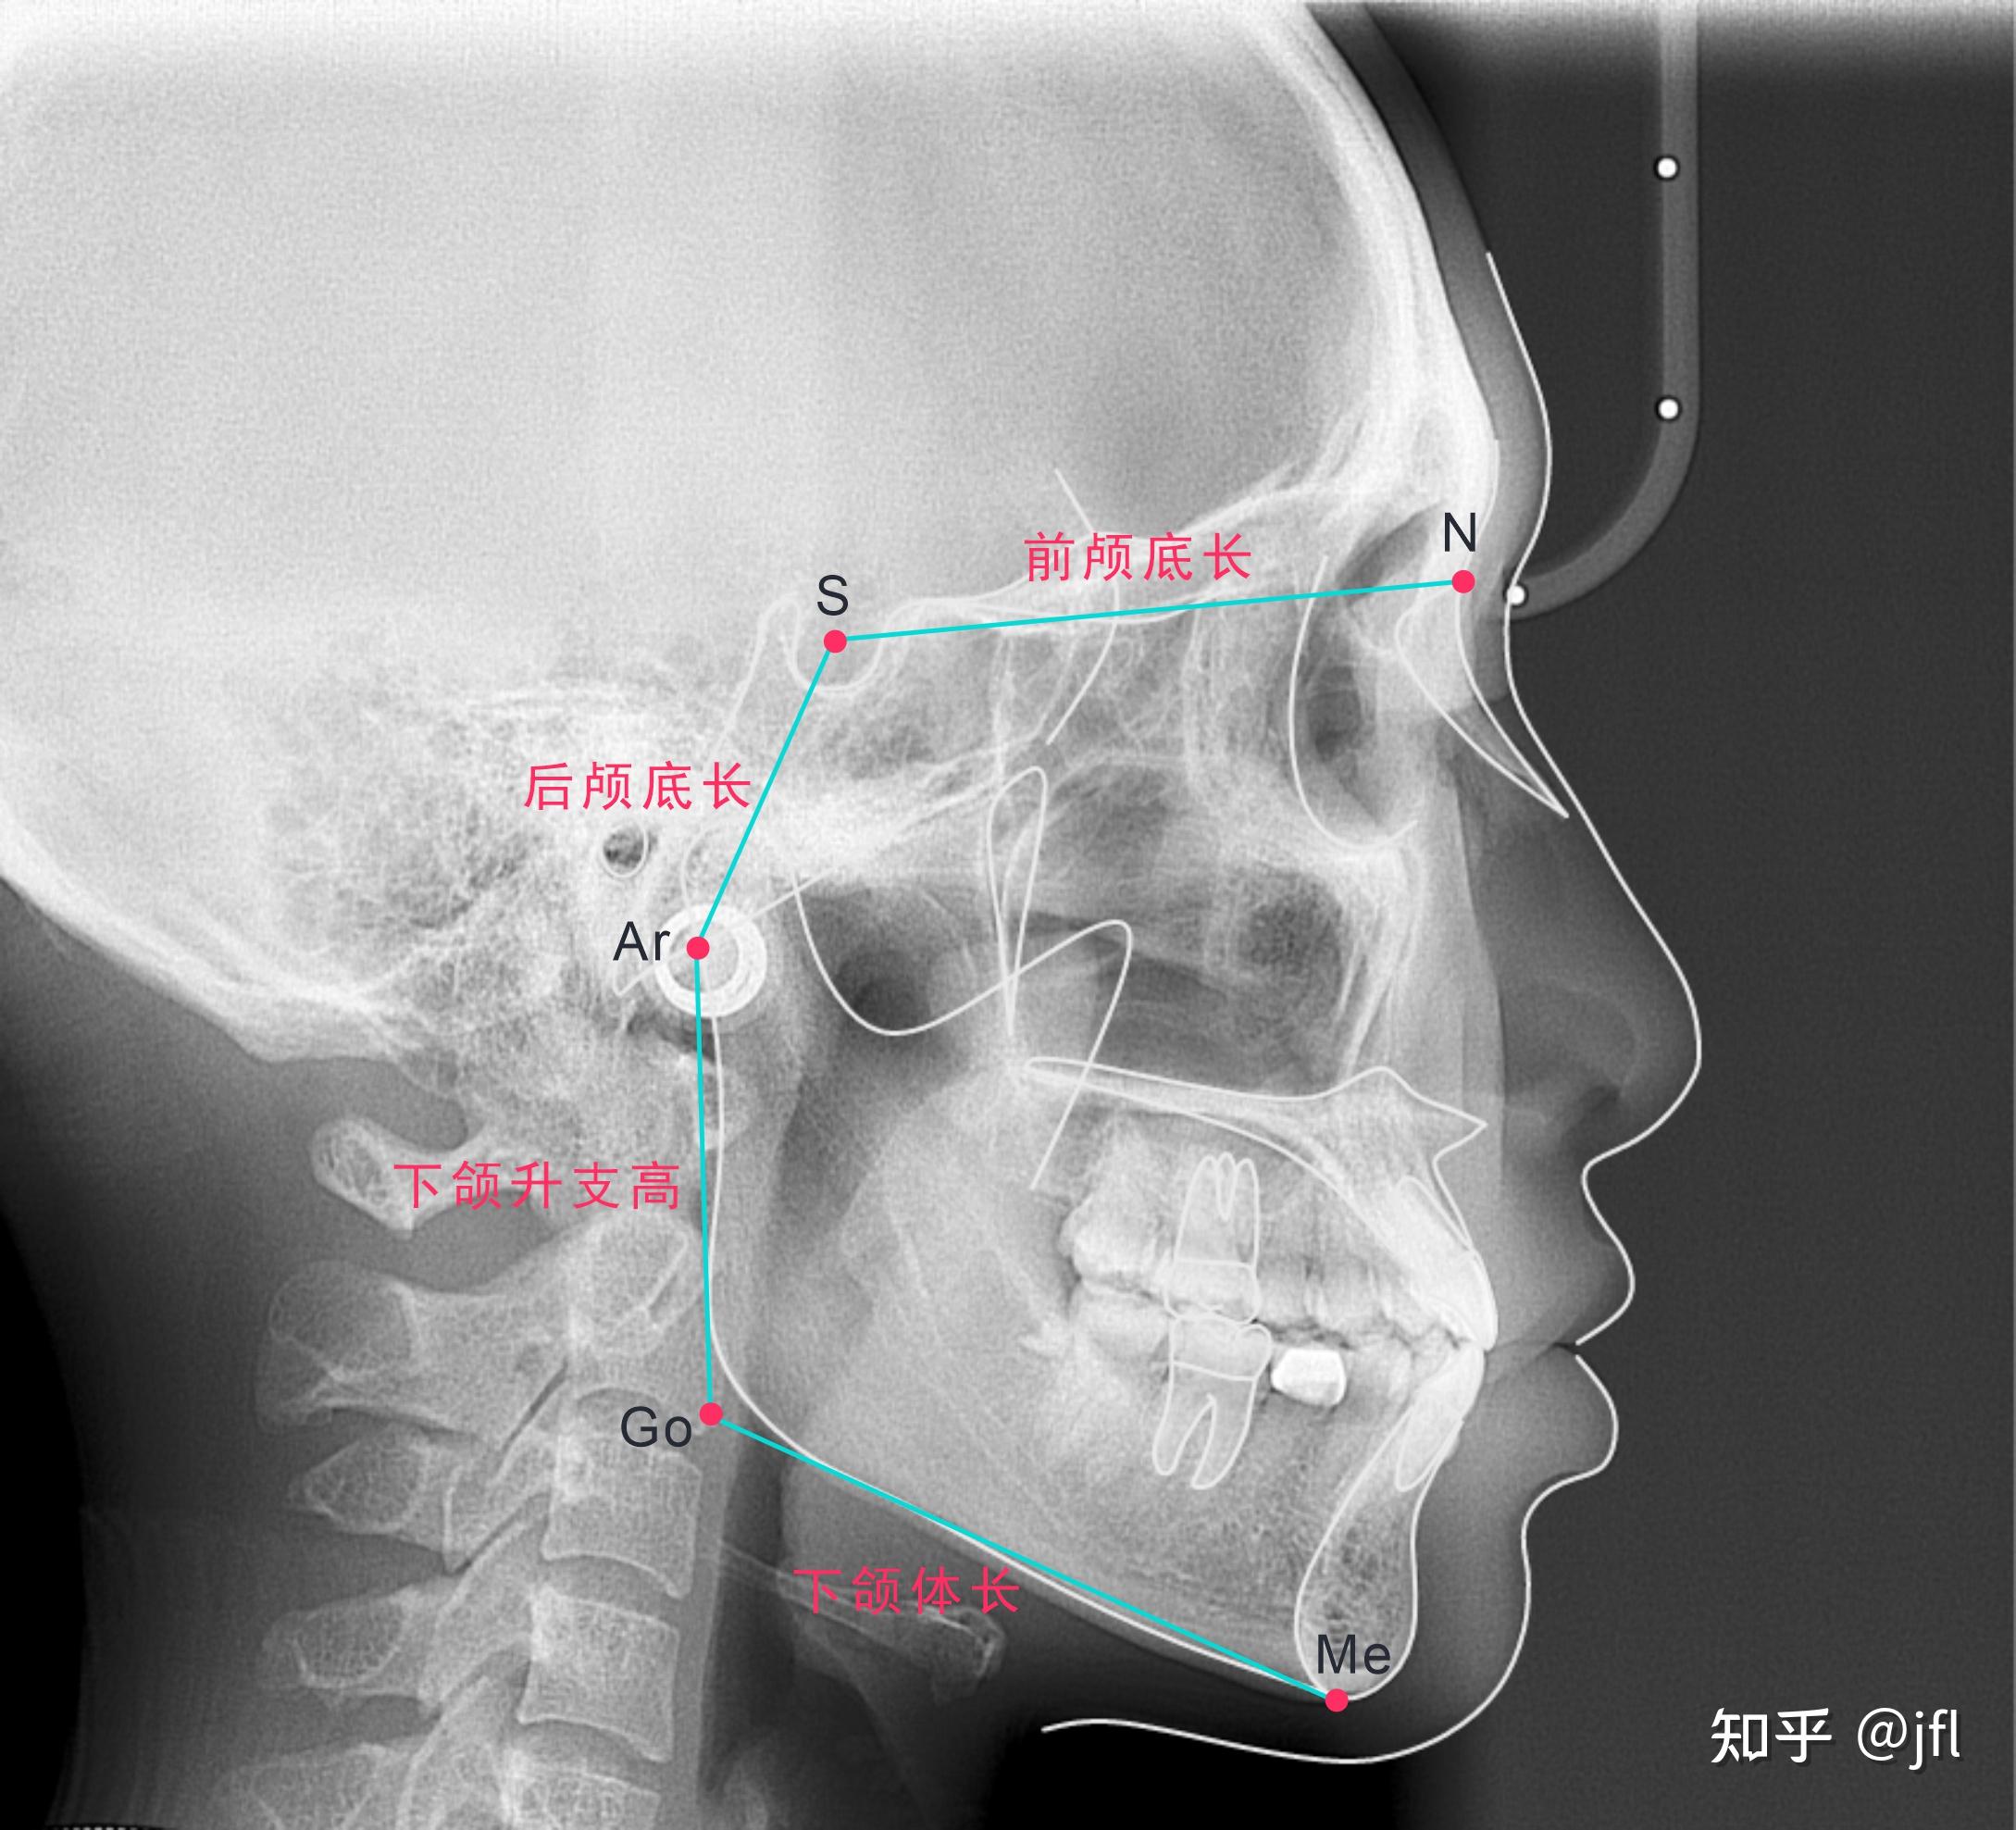

其中,go为重建下颌角点,下颌下缘和后缘切线的交点.

x线头影测量分析ppt